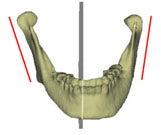

3차원 입체영상의 활용은 여러 가지 방향으로 가능한 반면 저자의 경우에는 안면비대칭 환자에서 “어느 구조물의 좌우 차이가 이부편위(chin deviation)를 야기하였는가”의 파악에 3차원 입체영상이 필요하였으며 이의 사용결과 2차원사진으로는 알 수 없었던 여러 가지를 이해할 수 있게 되었다. 얼핏 생각하면 이부편위는 좌우 ramus의 길이 차이 때문에 나타난다고 이해할 수 있다. 그러나 ramus 길이 뿐 아니라 mandibular body 길이차이에 의해서도 이부편위는 나타날 수 있고 이러한 부위별 파악은 특히 수술계획 수립에 매우 중요하다. 또한 어떤 환자에서는 ramus의 길이나 body의 길이는 좌우가 비슷한데, 정면에서 보았을 때 또는 측면에서 보았을 때 ramus의 경사도 차이로 인해 이부편위가 나타난 것을 발견할 수 있었다. 이러한 ramus 경사도 차이는 측모두부방사선사진이나 정모두부방사선사진에서도 관찰될 수 있지만 2차원적 사진의 경우 projection error로 인해 평가에 확신을 할 수 없는 반면 3차원 입체영상의 경우에는 이미지를자유자재로 돌려볼 수 있으므로 보다 용이하게 그리고 정확하게 이해를 할수 있었다. 3차원 입체영상을 통하여 외관상 보이는 이부편위의 원인을 살펴본 결과 저자는 (1)상악고경의 좌우차이 (2)ramus 길이의 좌우차이 (3)전방에서 보았을 때 좌우 ramus inclination의 차이 (4)측방에서 보았을 때 좌우 ramus inclination의 차이 (5)mandibular body 길이의  좌우차이 (6)mandibular body 윤곽의 좌우차이 등 6가지가 이부편위에 기여함을 발견할 수 있었다 (그림5).

그림 5. 이부편위에 기여하는 요인들. 이부편위는 단순히 ramus의 좌우차이에 의해서만 나타나는 것은 아니다. 3차원이미지를 자세히 관찰해 보면 상기 6가지 부위에서의 좌우차이가 환자로 하여금 "턱이 돌아갔다"고 느끼게 하고 있음을 알 수 있다. a. maxillary height; b. ramus length; c. frontal ramal inclination; d. lateral ramal inclination; e. body length; f. body height.